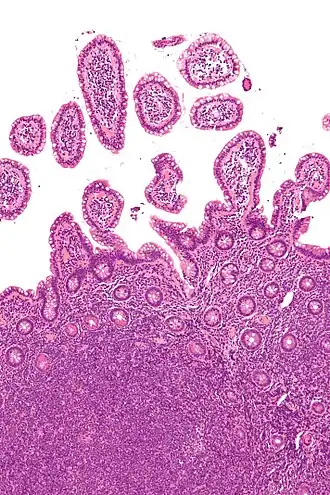

| Micrografia de linfoma de células de manto (parte inferior) em uma biópsia de íleo (H&E). | |